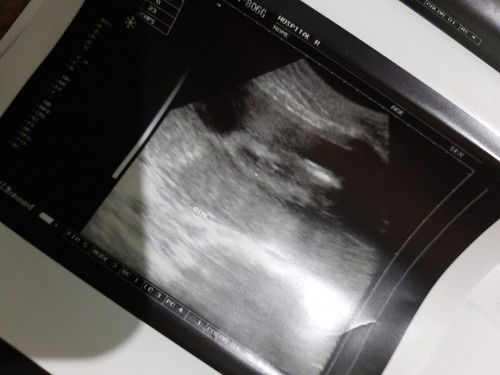

Girl or boy?

Hello mga mommy. Ask ko lang po sana sabi kasi parang babae daw nakikita nila at sabi parang burger daw pero need pa daw po ipaulit para sure ayaw po kasi ipakita ni baby ng maayos ang gender niya e. Dipo kasi ako marunong magbasa sa ultrasound . Girl po ba talaga?? 😊😊